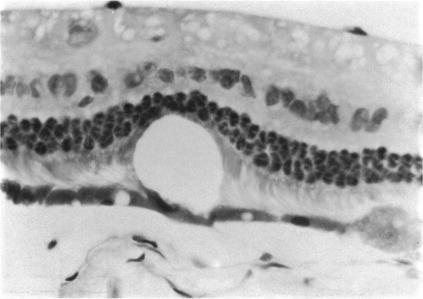

Reaction of the rabbit retinal pigment ipithelium to systemic lead poisoning.

Trans Am Ophthalmol Soc. 1974;72:404-47.